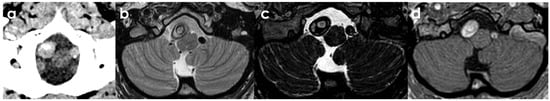

Figure 3.

Panel (a) shows NCCT, highlighting the right V4 VA-positive remodeling with a fusiform aneurysm characterized by an irregular hyperdense signal into the putative lumen on the axial plane. In panels (b–d), MRI shows the mural hematoma in the axial view [T2W TSE (b), T2W Drive (c), T1W Dixon (d)] confirming the different ages of the adjacent concentric strata of the hematoma and the sub-acute timing of the dissection, with a more prominent T2W and T1W hyperintensity.